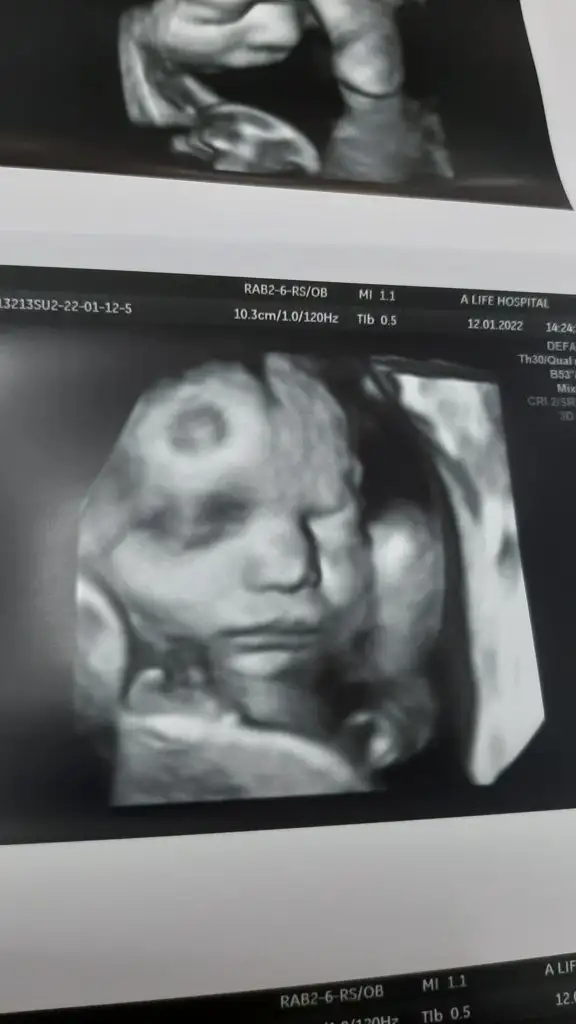

Maşallah canımBende bugün kontrole gittim, iri bir bebek olacak haftasından ileride dedi. Sezeryandan falan bahsetmedi hiç şimdiden, okudumda diyenler olmuş. Bakalım nasip artık